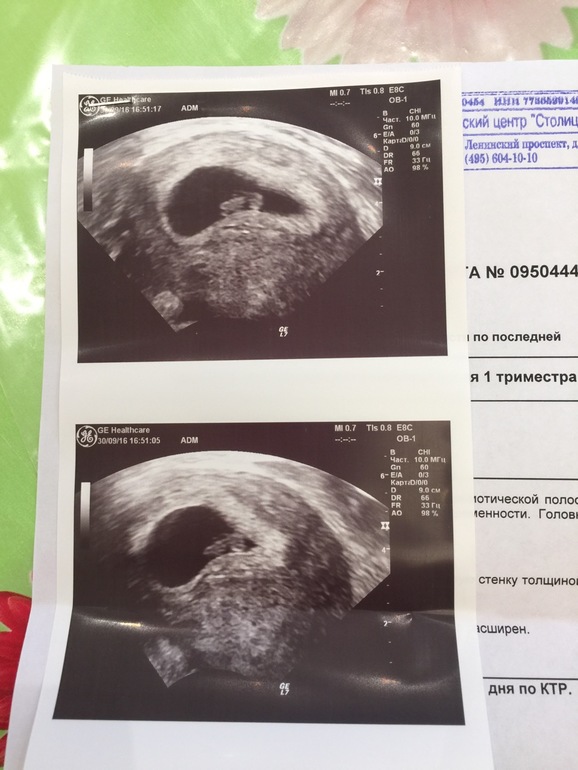

Фотографии на ранних этапах беременности